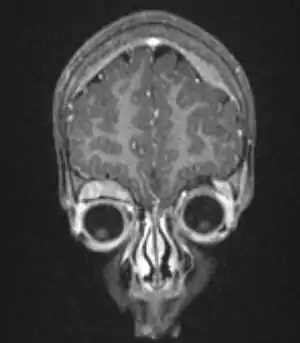

Нейробластома — злоякісна нейроендокринна пухлина, що походить з клітин нервового гребеня та може утворюватись з хромафіноцитів мозкової речовини надниркової залози, паравертебральних симпатичних гангліїв, парагангліїв симпатичної нервової системи.[3][4] Нейробластома є напоширенішим екстракраніальним новоутворенням педіатричного (дитячого) населення. Серед інших злоякісних пухлин у дітей частка нейробластоми становить до 10 %. Ця пухлина є однією з небагатьох утворень, що може спонтанно регресувати.[5] Естезіонейробластома, також відома як нейробластома, що походить з нюхового (ольфакторного) епітелію. Цей тип нейробластом виділяють окремо, оскільки вона не розвивається з клітин симпатичної нервової системи.[4] Найбільш поширеною локалізацією нейробластоми є мозкова речовина надниркових залоз, що визначається в 40 % випадків. Проте, нейробластома також може утворюватись, також, в будь-якій іншій тканині симпатичної нервової системи.